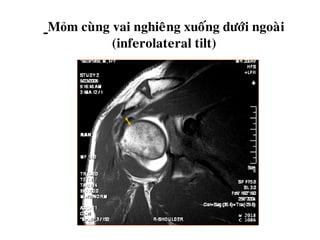

Mỏm cuøng vai nghieâng xuoáng döôùi ngoaøi

(inferolateral tilt)

Mỏm cuøng vainghieâng xuoáng döôùi ngoaøi (inferolateral tilt)